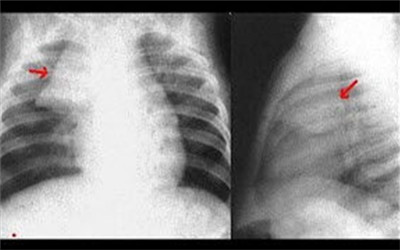

1、X線檢查:心髒陰影大小正常或稍大,心增大可能由於心包增厚或伴有心包積液,左右心緣正常弧弓消失,呈平直僵硬,心髒搏動減弱,上腔靜脈明顯增寬,部分病人心包有鈣化呈蛋殼狀,此外,可見心房增大。